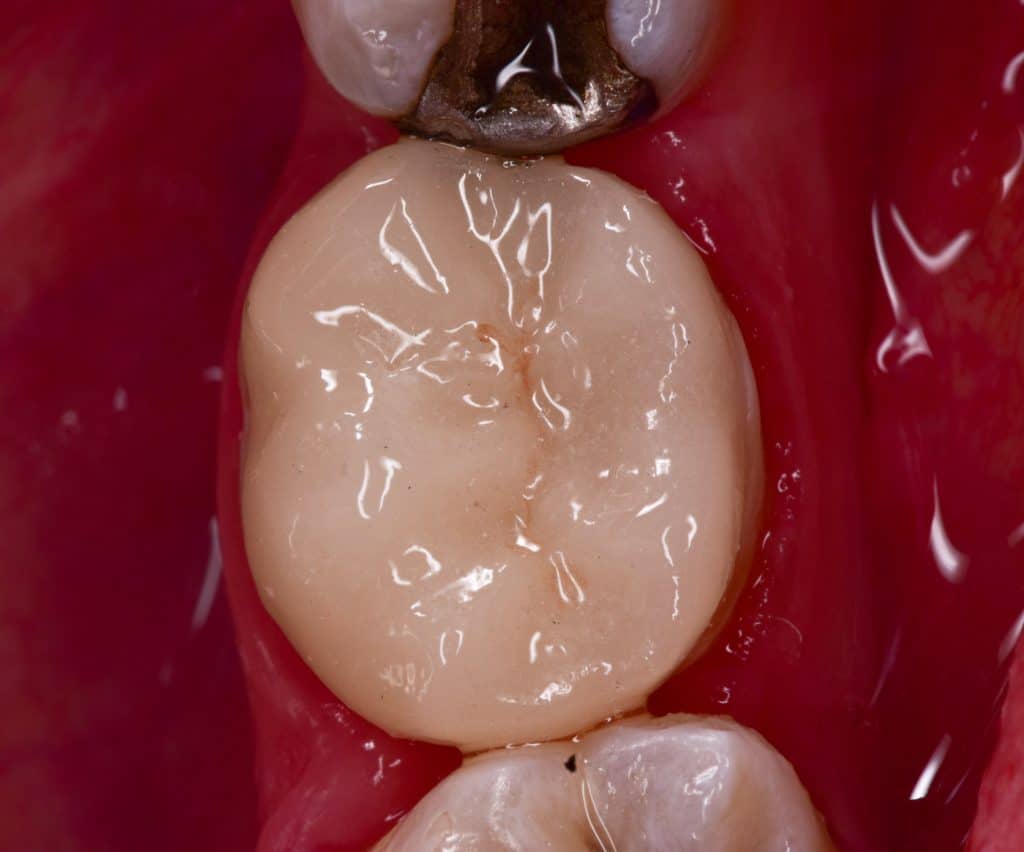

Immediate result

Immediate after rubber dam removal